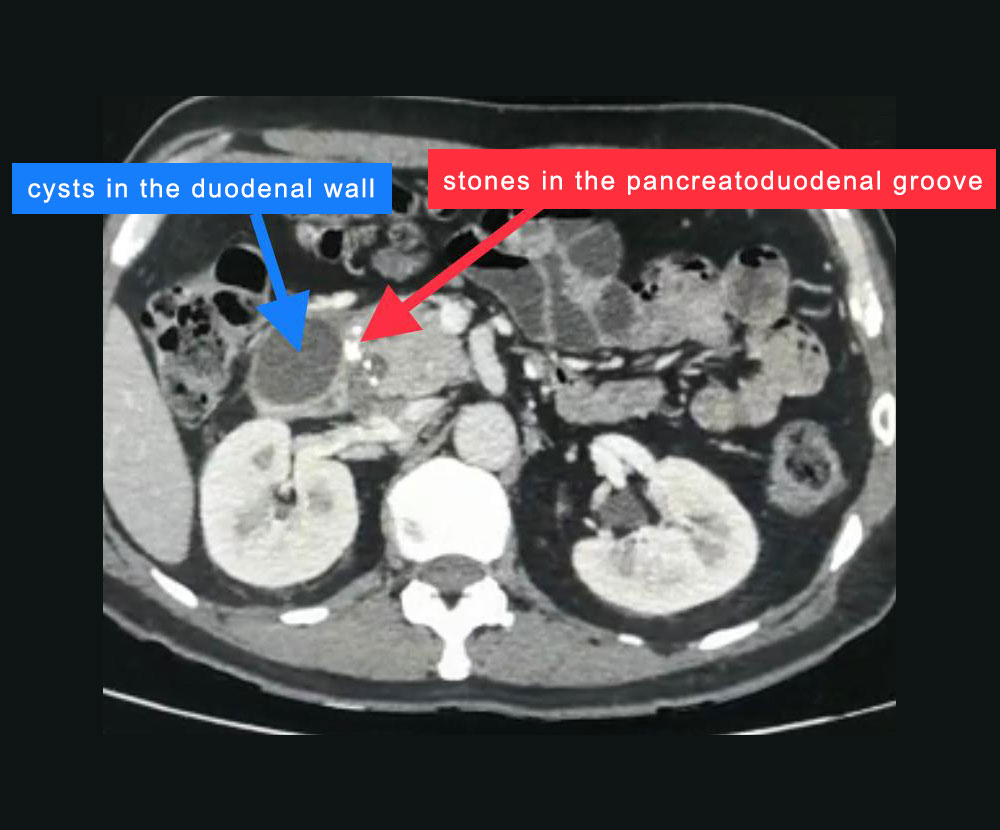

45 year old gentleman with recurrent abdominal pain on the background of alcohol intake was diagnosed to have chronic pancreatitis with pancreatic calculi and was referred to LPC for further management. On further investigation he was found to have an otherwise uncommon type of chronic pancreatitis known as groove pancreatitis and cystic duodenal dystrophy.

These patients peculiarly develop inflammation between head of pancreas and adjoining duodenum (groove). The rest of pancreas develops changes of mild chronic pancreatitis like mild duct dilatation and occasional stone in the duct. However major changes are in the groove. In the advanced form of this problem, there is severe fibrosis in the groove which may lead to the narrowing of bile duct and duodenum leading to jaundice and bowel obstruction. Similarly there can be narrowing of or clotting in the portal vein which carries blood from intestines to liver. Sometimes pancreatic cancer starts in this inflammation and is very difficult to diagnose even after extensive investigations. In rare situation there are cystic changes in the wall of the adjoining duodenum also called as cystic dystrophy. It is very uncommon form of chronic pancreatitis. We happen to have treated groove pancreatitis and cystic dystrophy both before and reported it in the international journal.

This problem is especially associated with patients having alcohol abuse and our gentleman had developed significant cystic dystrophy of duodenal wall causing abdominal pain and vomiting (due to luminal obstruction).